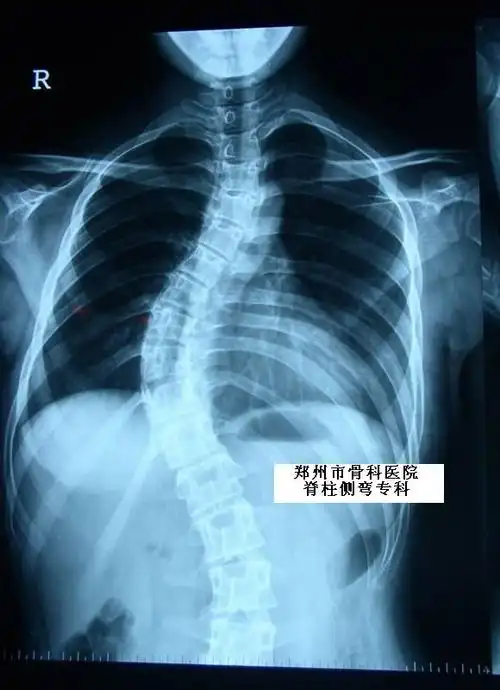

凸侧加压,同时去旋转的原则矫正脊柱的冠状面,矢状面及轴面的三维畸形